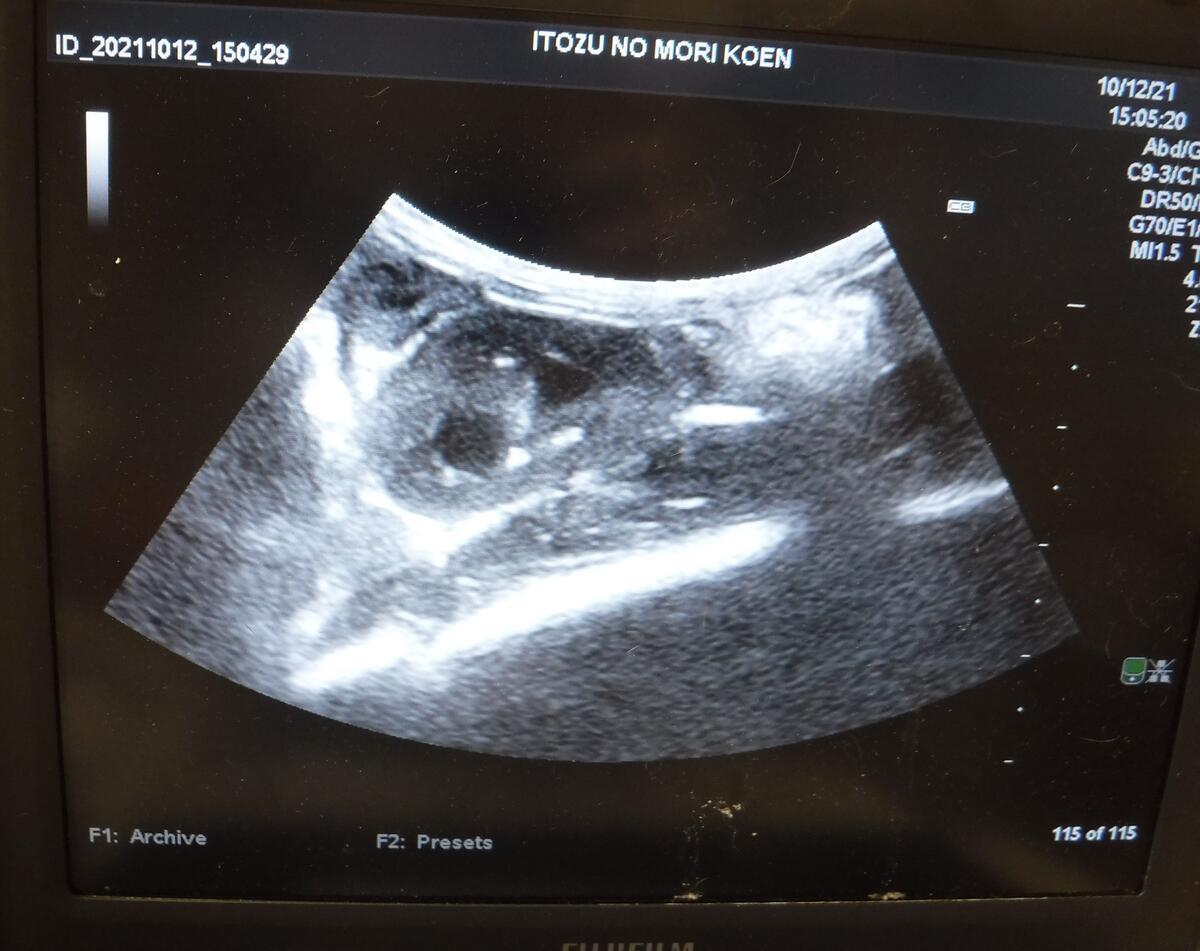

しかし、口唇は動かす部位なので、なかなかくっつかず、麻酔をかけて再縫合になってしまいました。その際に健康診断を兼ねて、血液検査と超音波検査、レントゲン検査も行います。